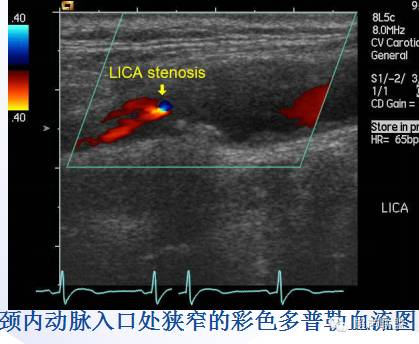

2、CDFI及PW:(注意检测双侧颈动脉血流频谱)

CDFI见动脉狭窄所致湍流,闭塞者无血流信号。

PW可见外周动脉狭窄的频谱特征,主要指标有PSV、EDV、PSVICA/PSVCCA。(狭窄程度判断见下表)

50—69% | 有明显斑块 | 125-230 | 40-100 | 2.0-4.0 |

>70%,但不到接近闭塞 | 有斑块伴有管腔狭窄 | >230 | >100 | >4.0 |